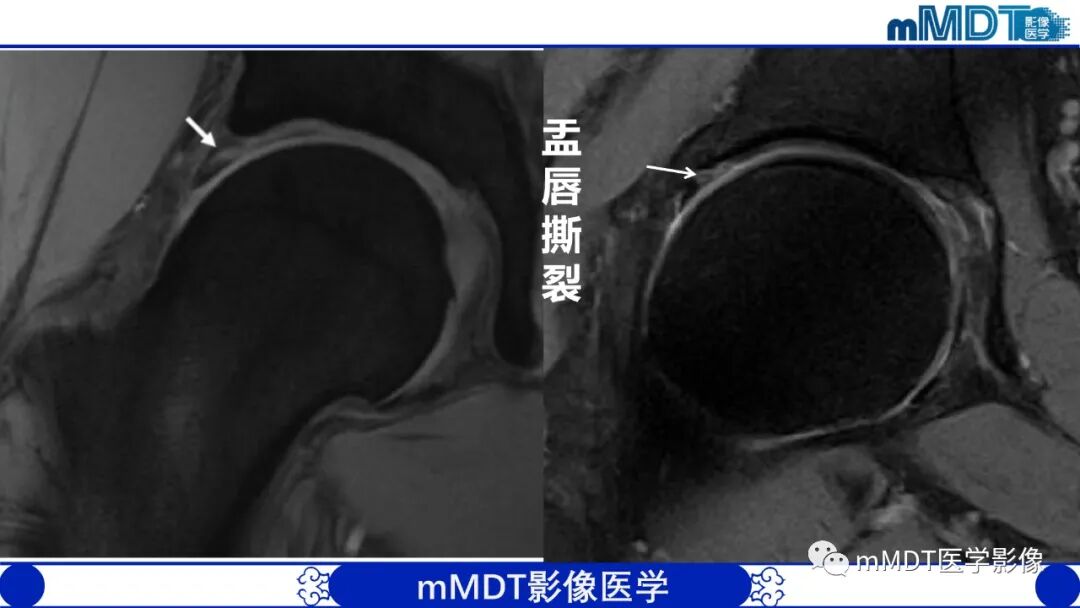

髂腰肌撞击症它是导致腹股沟区疼痛的常见原因之一。髂腰肌撞击症相关盂唇损伤直接位于前方,位置位于3点钟方向。